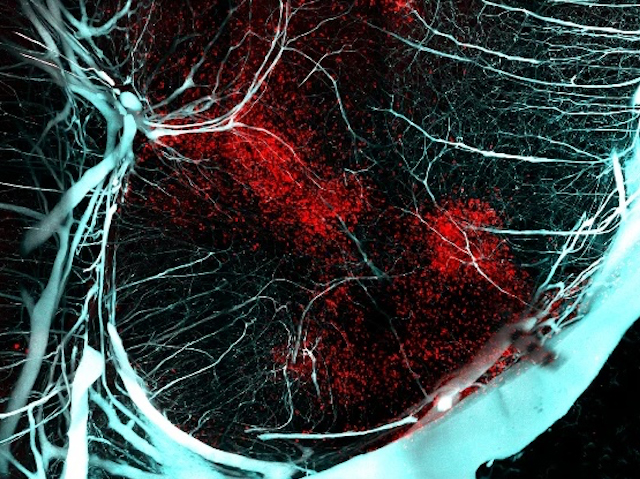

No t'interessa tindre l'advocat a l'escena del crim. Es dediquen a escarotar, malversar evidències i empitjorar la situació per a tots. Però després són essencials per a consolidar situacions i construir ponts trencats. Un nou estudi ha trobat una utilitat similar durant temps limitats de les cèl·lules immunitàries, els neutròfils, al cervell després de lesions causades per falta d'oxigen a nounats. Els neutròfils es donen pressa en entrar en escena i si es queden massa, empitjoren la inflamació i causen danys. Però unes noves anàlisis mostren que apareixen en dues onades: la primera causa caos, però després arriben en una forma distinta (a la imatge, en roig a una secció de cervell de ratolí 7 dies després de la lesió), per ajudar als vasos sanguinis a recréixer, reparar els nervis i perquè es recupere el cervell. Aquest estudi fins i tot identifica una proteïna, la GM-CSF, que pot promoure més neutròfils cap a aquesta forma més productiva. Açò obri la porta a noves intervencions immunitàries en estadis específics, en situacions en què els tractaments actuals estarien limitats i podries conduir a una vida de discapacitat o mort.

Imatge publicada originalment sota una llicència Creative Commons (CC BY 4.0)